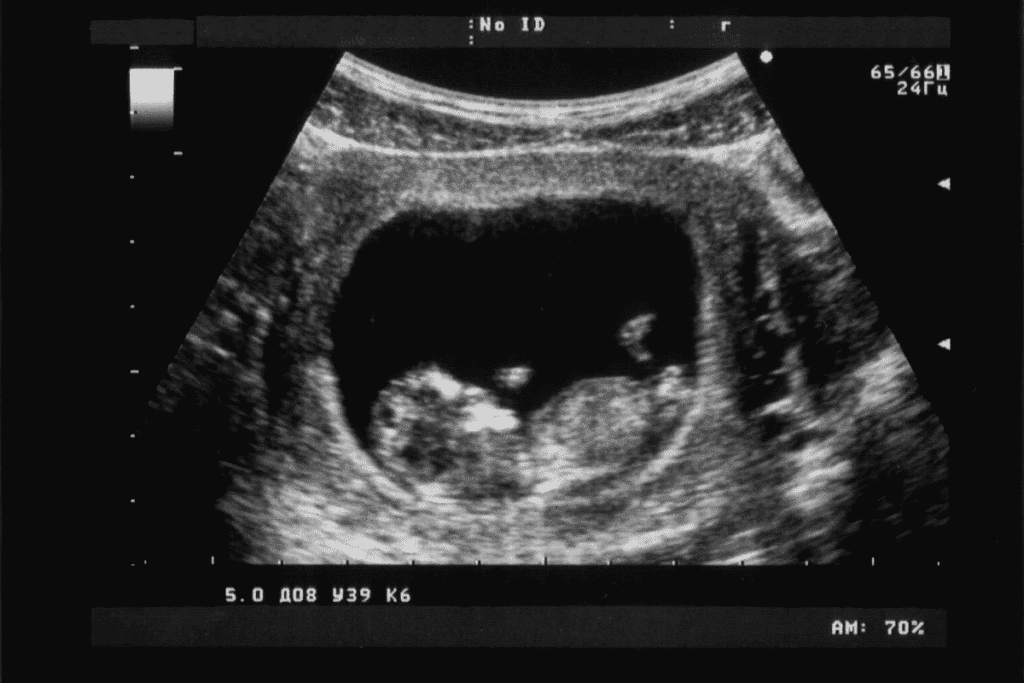

An 8 weeks pregnant sonogram is often the first detailed look at your developing baby. For many parents, the first sonogram at 8 weeks confirms pregnancy viability, detects the fetal heartbeat, and establishes an accurate due date.

At this stage, the embryo measures about 1 inch long and key structures such as the gestational sac, fetal pole, and early heartbeat are typically visible.

Knowing what can you see at 8 week ultrasound is helpful. At this time, you can see the gestational sac, fetal pole, and even the heartbeat. It gives a peek into the early stages of fetal development.

Physical Appearance of Your 8-Week-Old Fetus

The 8-week fetus is about 1 inch long and looks like a bean. It has grown a lot and looks very different now.

Size Comparison

An 8-week-old fetus is 1 inch long, like a small gummy bear or bean. This helps parents imagine how big it is.

The “Gummy Bear” or Bean Shape

The fetus looks like a bean or small gummy bear because of its curved shape. This shape comes from its fast growth in the eighth week.

Distinguishing Head from Body

At 8 weeks, the fetus’s head is bigger than its body. It looks more rounded. The head and body are easy to tell apart. This is a key time for organ and system growth.

At 8 weeks, an ultrasound shows the gestational sac, fetal pole, and heartbeat. The fetus looks like a bean or a small gummy bear, about 1 inch long.